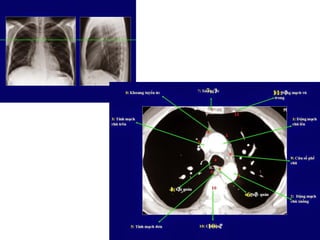

1. Khôùp öùc-ñoøn

2. Tónh maïch thaân caùnh tay ñaàu (T)

3. Cung ñoäng maïch chuû

4. Cöûa soå pheá chuû

5. Ñoäng maïch phoåi (T)

6. Thaân vaø ñoäng maïch phoåi (P)

7. Nhó (T)

8. Caùc buoàng tim

9. Khoang sau chaân hoaønh

CAÙC MAËT CAÉT CÔ BAÛN TRUNG THAÁT